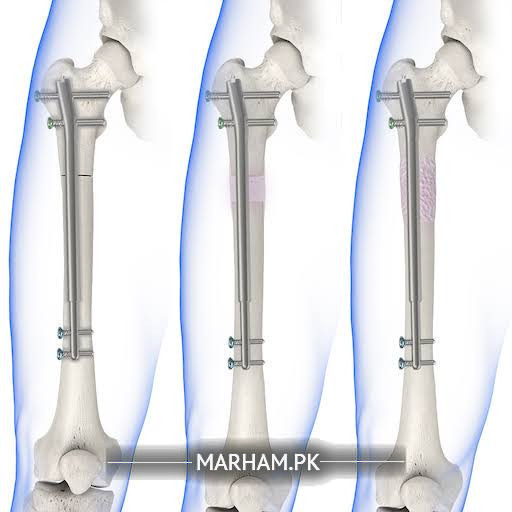

assalaam o alikam. mein ne precice surgery karwani hai lemb lengthening k liye. jo doctor sahib kartay hain wo inform kar dein mein un ki online appointment book karwa kr details leta hon.

actually this type of nail needs magnetic imaging for lengthening ,so far this whole set up are not available here.

what we do ,is by putting a nail to maintain alignment and external fixator(out side the skin) for distraction/lengthening....

book an appointment with me for consultation. I do it with illizarove technique

kia aap muje bata saktay hain k aap LON and precice 2.0 limb lengthening surgery kartay hain?